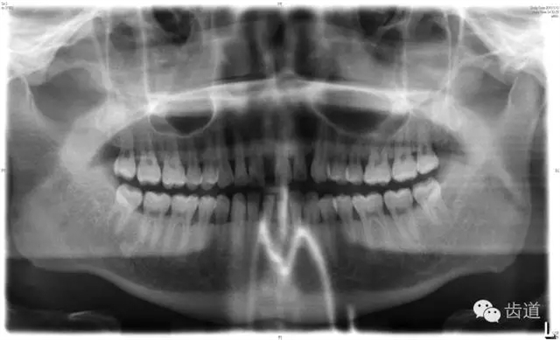

X線:根尖片、曲面斷層片(牙槽嵴頂,水平垂直吸收,程度)